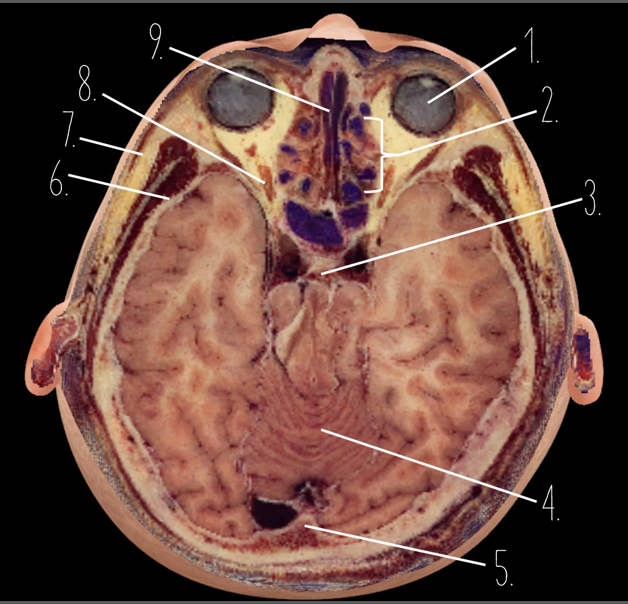

1

Frontal Bone

2

Frontal Lobe

3?

Falx Cerebri

4?

Gray Matter

5?

White Matter

6?

Sulcus

7?

Gyrus

8?

Fissure